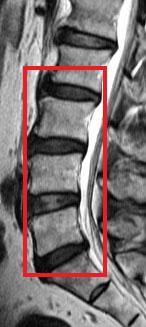

今次的研究是一項以南中國地區人口而作出的具代表性抽樣研究,從上述大型人口群組中抽出21歲或以上的成年人為研究對象。在是次的研究中,研究人員分析了合共2,599位成年人的磁力共振(MRI)檢查數據。當中27%(709人)沒有椎間盤退化,而73%(1,809人)則有椎間盤退化。在患有椎間盤退化的成年人當中,有7%體重過輕,48%體重正常,36%過重和9%肥胖。超重及肥胖的成年人出現椎間盤退化程度及發展成更嚴重的病徵的機會,比正常體重或過輕的成年人嚴重。